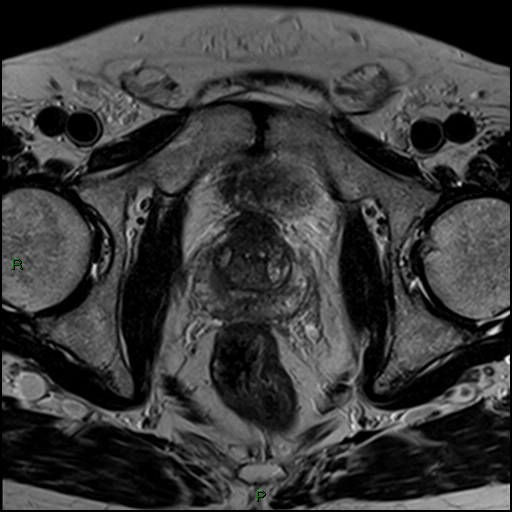

• Khối u bàng quang

U cơ trơn bàng quang (Leiomyoma of the urinary bladder)

Ung thư biểu mô tế bào chuyển tiếp ở bàng quang (Transitional cell carcinoma (urinary bladder))

Phân loại giai đoạn ung thư của bàng quang (Transitional cell carcinoma of the bladder (staging))

Ung thư biểu mô tuyến của bàng quang (Adenocarcinoma urinary bladder)